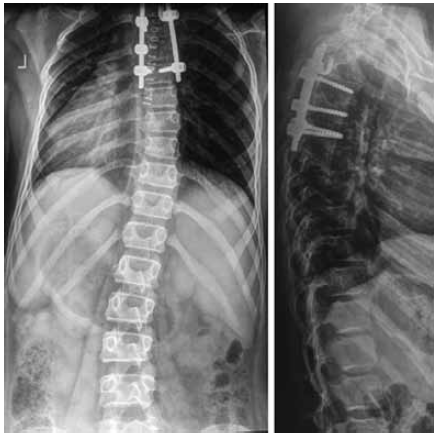

After the surgical treatment, control radiographs revealed a radical corrected local congenital spinal deformity in upper thoracic region, the multi-support surgical hardware (4 transpedicular support elements and 1 infra-laminar support hook) installed in the vertebrae Th3, Th5, and Th6 were correct and stable. Right-sided scoliotic arch at the level of the vertebrae Th7–Th10 was 15°, and the left-sided arch at the level of L1–L4 was 11° (Fig. 2).

Fig. 2. Radiographs of the spine of the patient F., 11 years old, in two views after the surgical treatment

After the surgical treatment, a completely corrected congenital local arch of curvature at the level of the posterolateral hemivertebra and reduced scoliotic deformity arches in the thoracic and lumbar regions were recorded. The size of the thoracic kyphosis was 38°, whereas that of lumbar lordosis was 42°, according to Cobb, and it was within the physiological norm. Besides, the laminar hook was installed on the concave side of the curvature at the level of the posterolateral hemivertebra due to the small size of the base of the arch of the vertebra Th3 and Th2, which did not allow the transpedicular screw to be inserted.